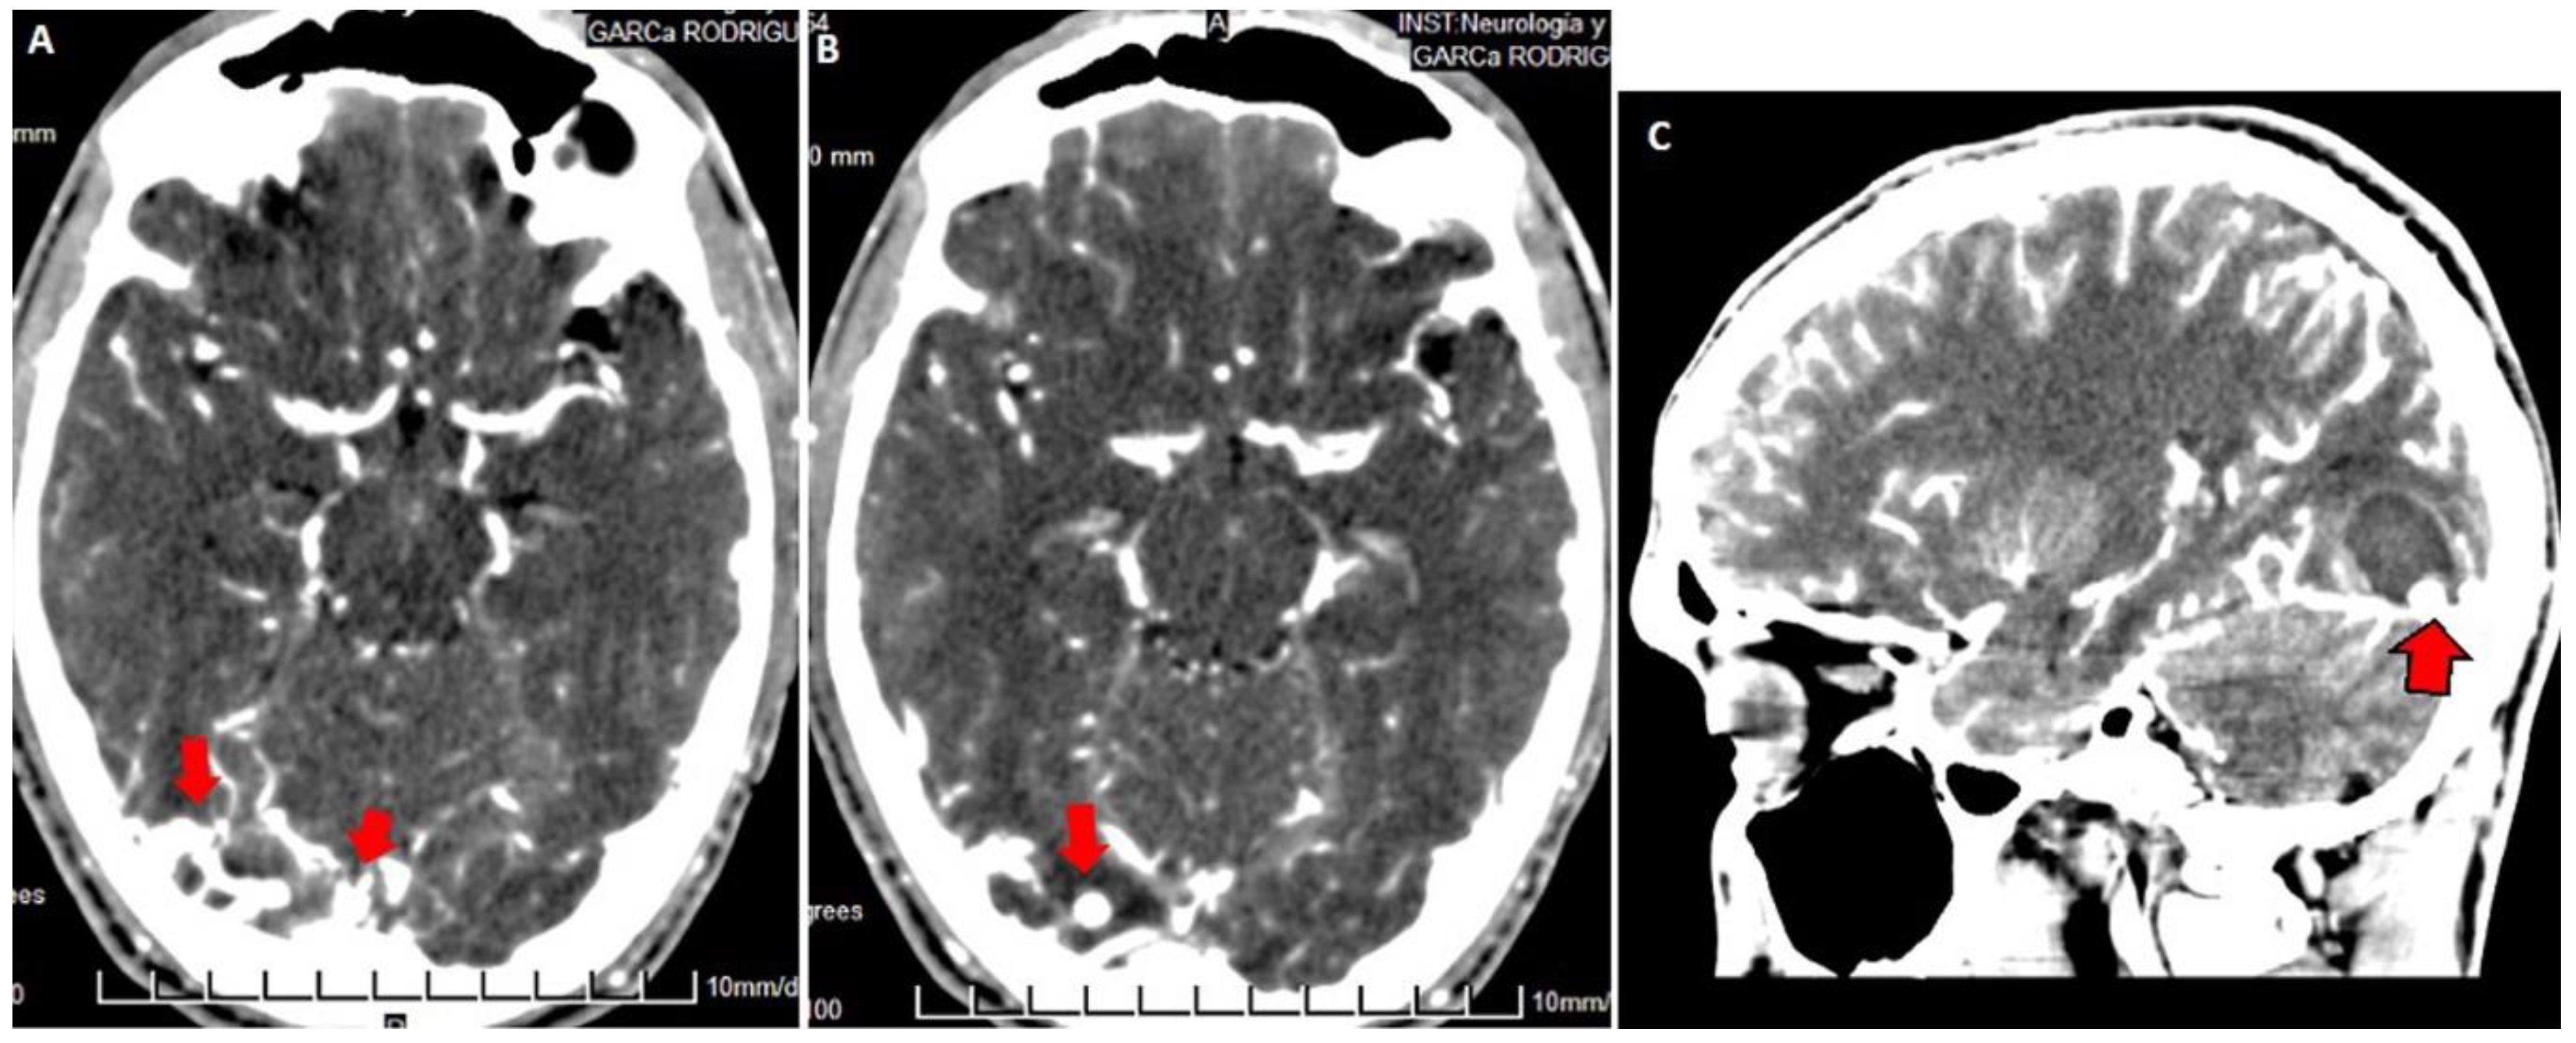

Both hematomas were reabsorbed gradually (Figure 2), with satisfactory clinical evolution after a two-month follow-up period. Figure 2 shows the increased frontal subdural hematoma and its extension to parietal and frontal lobes. Angiography revealed ecstatic cortical veins, one of them with saccular dilatation adjacent to the IPH (Figure 3). For this reason, we decided to perform cerebral angiography, which confirmed the dural arteriovenous fistula. It connected the artery, a branch of the external carotid artery, with cortical veins in the superior sagittal sinus drainage (Figure 4). After endovascular therapy, the evolution of the patient was satisfactory (Figure 5 and Figure 6). Two years later, no bleeding had appeared, and the subsequent angiographic studies were negative.

Figure 3.

Contrasted brain CT: in axial section (A,B) dilated vessels are observed in the right occipital region (red arrows in (A)) with saccular venous ectasia (red arrows in (B,C)). Sagittal reconstruction (C) shows intraparenchymal hematoma in resolution with a ring-like enhancement on its periphery. The dilated saccular vein is in contact with the lower edge of the hematoma (red arrow with a black border).